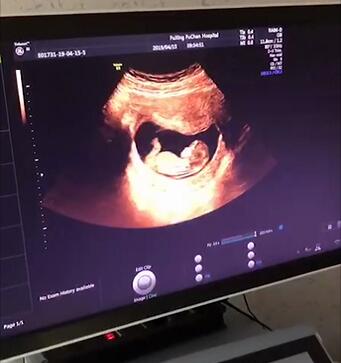

④.B超:早期B超检查可以确定是否宫内妊娠,或多胎妊娠,还可排除宫外孕、葡萄胎,排除子宫内异位妊娠(如切口妊娠、宫角妊娠、宫颈妊娠、子宫肌层妊娠等),并核实孕周。

NT检查是指,胎儿颈后部皮下组织内液集聚的厚度的检查。通过B超手段测量胎儿颈项部皮下无回声透明层较厚的部位,目的是在妊娠较早阶段诊断染色体疾病和发现多种原因造成的胎儿异常,是排除胎儿畸形的一种常规检查。

NT检查还能检测胎儿的生长发育情况、胎盘环境、子宫状况等。

NT检查有严格的时间要求(11w-13w+6d),14周以后做会影响到筛查的准确性,所以妈妈们一定不要错过时间。